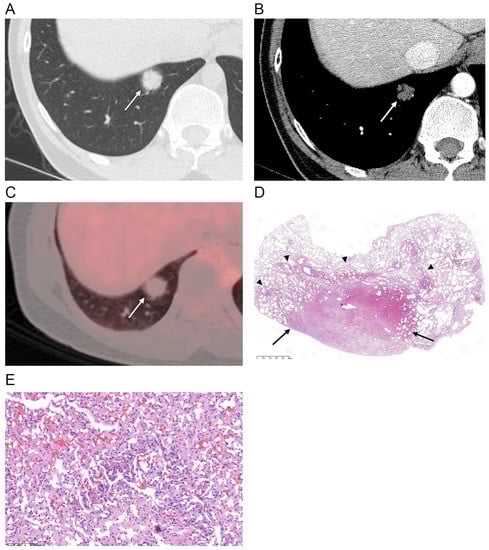

| Nodule density | |

| Ground-glass | 1 (6) |

| Part-solid | 15 (88) |

| Solid | 1 (6) |

| Contour | |

| Smooth | 16 (94) |

| Margin | |

| Well-defined | 8 (47) |

| Ill-defined | 9 (53) |

| Perivascular lucency | 2 (12) |

| Air bronchogram | 10 (59) |

| Enhancement ** | |

| Hypoattenuation | 14 (93) |